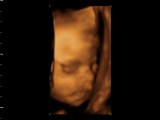

ELVİN 28.HAFTA